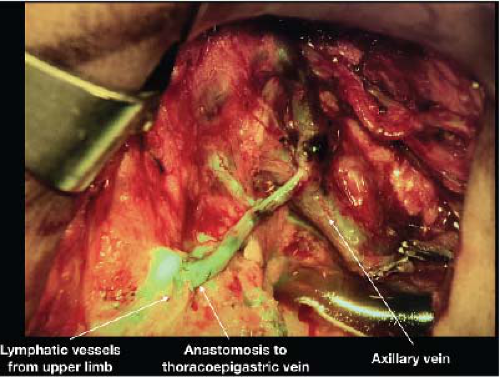

LVB is a minimally invasive outpatient procedure where an obstructed lymphatic vessel is divided and anastomosed to a neighboring vein through one or several small incisions (Fig. 25-2). These vessels are typically 0.3 to 0.8 mm

in diameter making LVB technically challenging. In general, distal LVB is most effective in patients with early lymphedema evidenced by presence of linear lymphatics on ICG. An LVB performed on a heavily scarred lymphatic vessel is not going to be as effective. More recently, immediate lymphatic reconstruction with LVB in the axilla at the time of lymphadenectomy is being performed in the hopes of reducing the risk of lymphedema (Fig. 25-3) (14). Data in this field is still preliminary and also under study protocol at our institution.

![]() FIGURE 25-3 Immediate lymphatic reconstruction at the time of axillary dissection with lymphovenous bypass of several lymphatic vessels telescoped into the thoracoepigastric vein. |